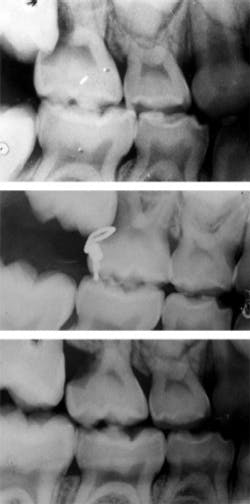

Three of the permanent first molars have erupted in your seven-year-old patient. Where is tooth No. 3? Upon exposing routine bitewings, you find that pesky molar resorbing the distal portion of the upper right primary second molar. This evidence of ectopic eruption may or may not warrant additional radiography. But it is crucial that a decision is made about what can be done to arrest or correct this process.

A viable option is the extraction of tooth A in order to allow for eruption of tooth No. 3. The lost space can then be gained with orthodontia, with hopes that No. 4 will erupt without compromise. An orthodontic consultation, however, should be considered prior to the extraction. Another option is the brass wire technique, as demonstrated in Figure 1.